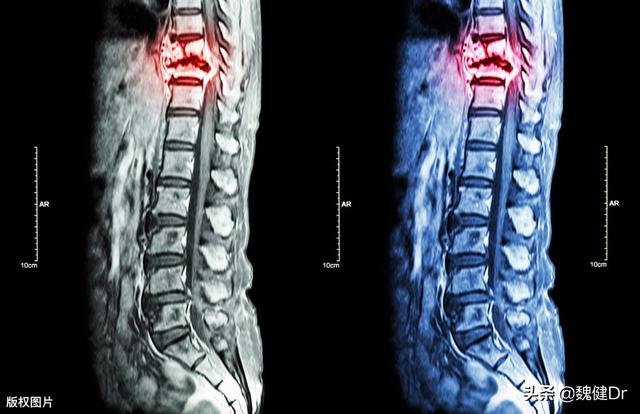

神经源性损伤最常见的是腰椎间盘突出症,腰椎间盘突出症是由于长时间的姿势不当导致腰椎周围的肌肉紧张,继而进一步的松弛、腰椎不稳,出现椎间盘突出压迫神经造成腰痛、屁股痛、屁股麻、腿麻等症状。

早期的腰椎间盘突出症可以通过药物保守治疗,包括止痛,松弛肌肉,还有营养神经。严重的腰椎间盘突出症,保守治疗没有效果,需要手术治疗。至于周围神经病变的有可能是神经纤维瘤等神经的问题。鉴别到底是神经源性损伤还是周围神经病变可以通过肌电图来实现。